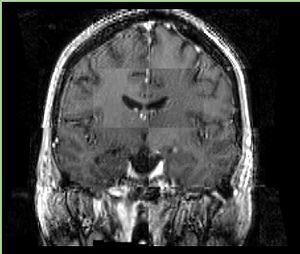

• Checkerboard appearance of unregistered images for the representative data of interest

• Case03